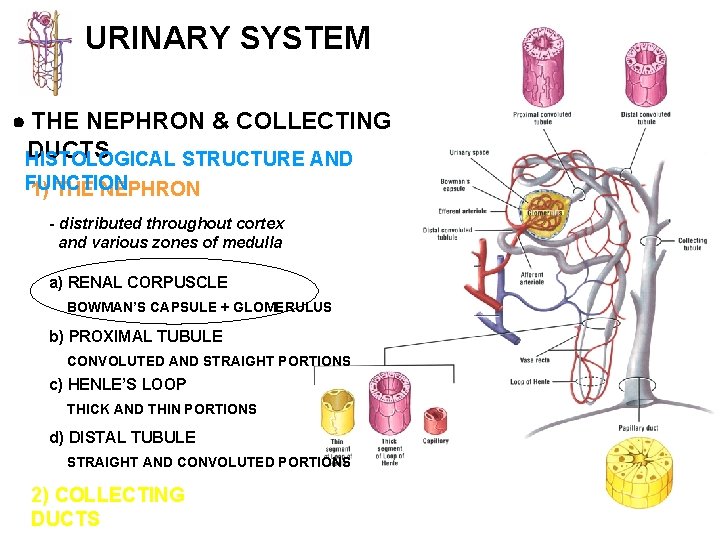

URINARY SYSTEM THE NEPHRON & COLLECTING DUCTS 1) THE NEPHRON - distributed throughout cortex and various zones of medulla a) RENAL CORPUSCLE BOWMAN’S CAPSULE + GLOMERULUS b) PROXIMAL TUBULE CONVOLUTED AND STRAIGHT PORTIONS c) HENLE’S LOOP THICK AND THIN PORTIONS d) DISTAL TUBULE STRAIGHT AND CONVOLUTED PORTIONS 2) COLLECTING DUCTS

URINARY SYSTEM THE NEPHRON & COLLECTING DUCTS HISTOLOGICAL STRUCTURE AND FUNCTION 1) THE NEPHRON - distributed throughout cortex and various zones of medulla a) RENAL CORPUSCLE BOWMAN’S CAPSULE + GLOMERULUS b) PROXIMAL TUBULE CONVOLUTED AND STRAIGHT PORTIONS c) HENLE’S LOOP THICK AND THIN PORTIONS d) DISTAL TUBULE STRAIGHT AND CONVOLUTED PORTIONS 2) COLLECTING DUCTS